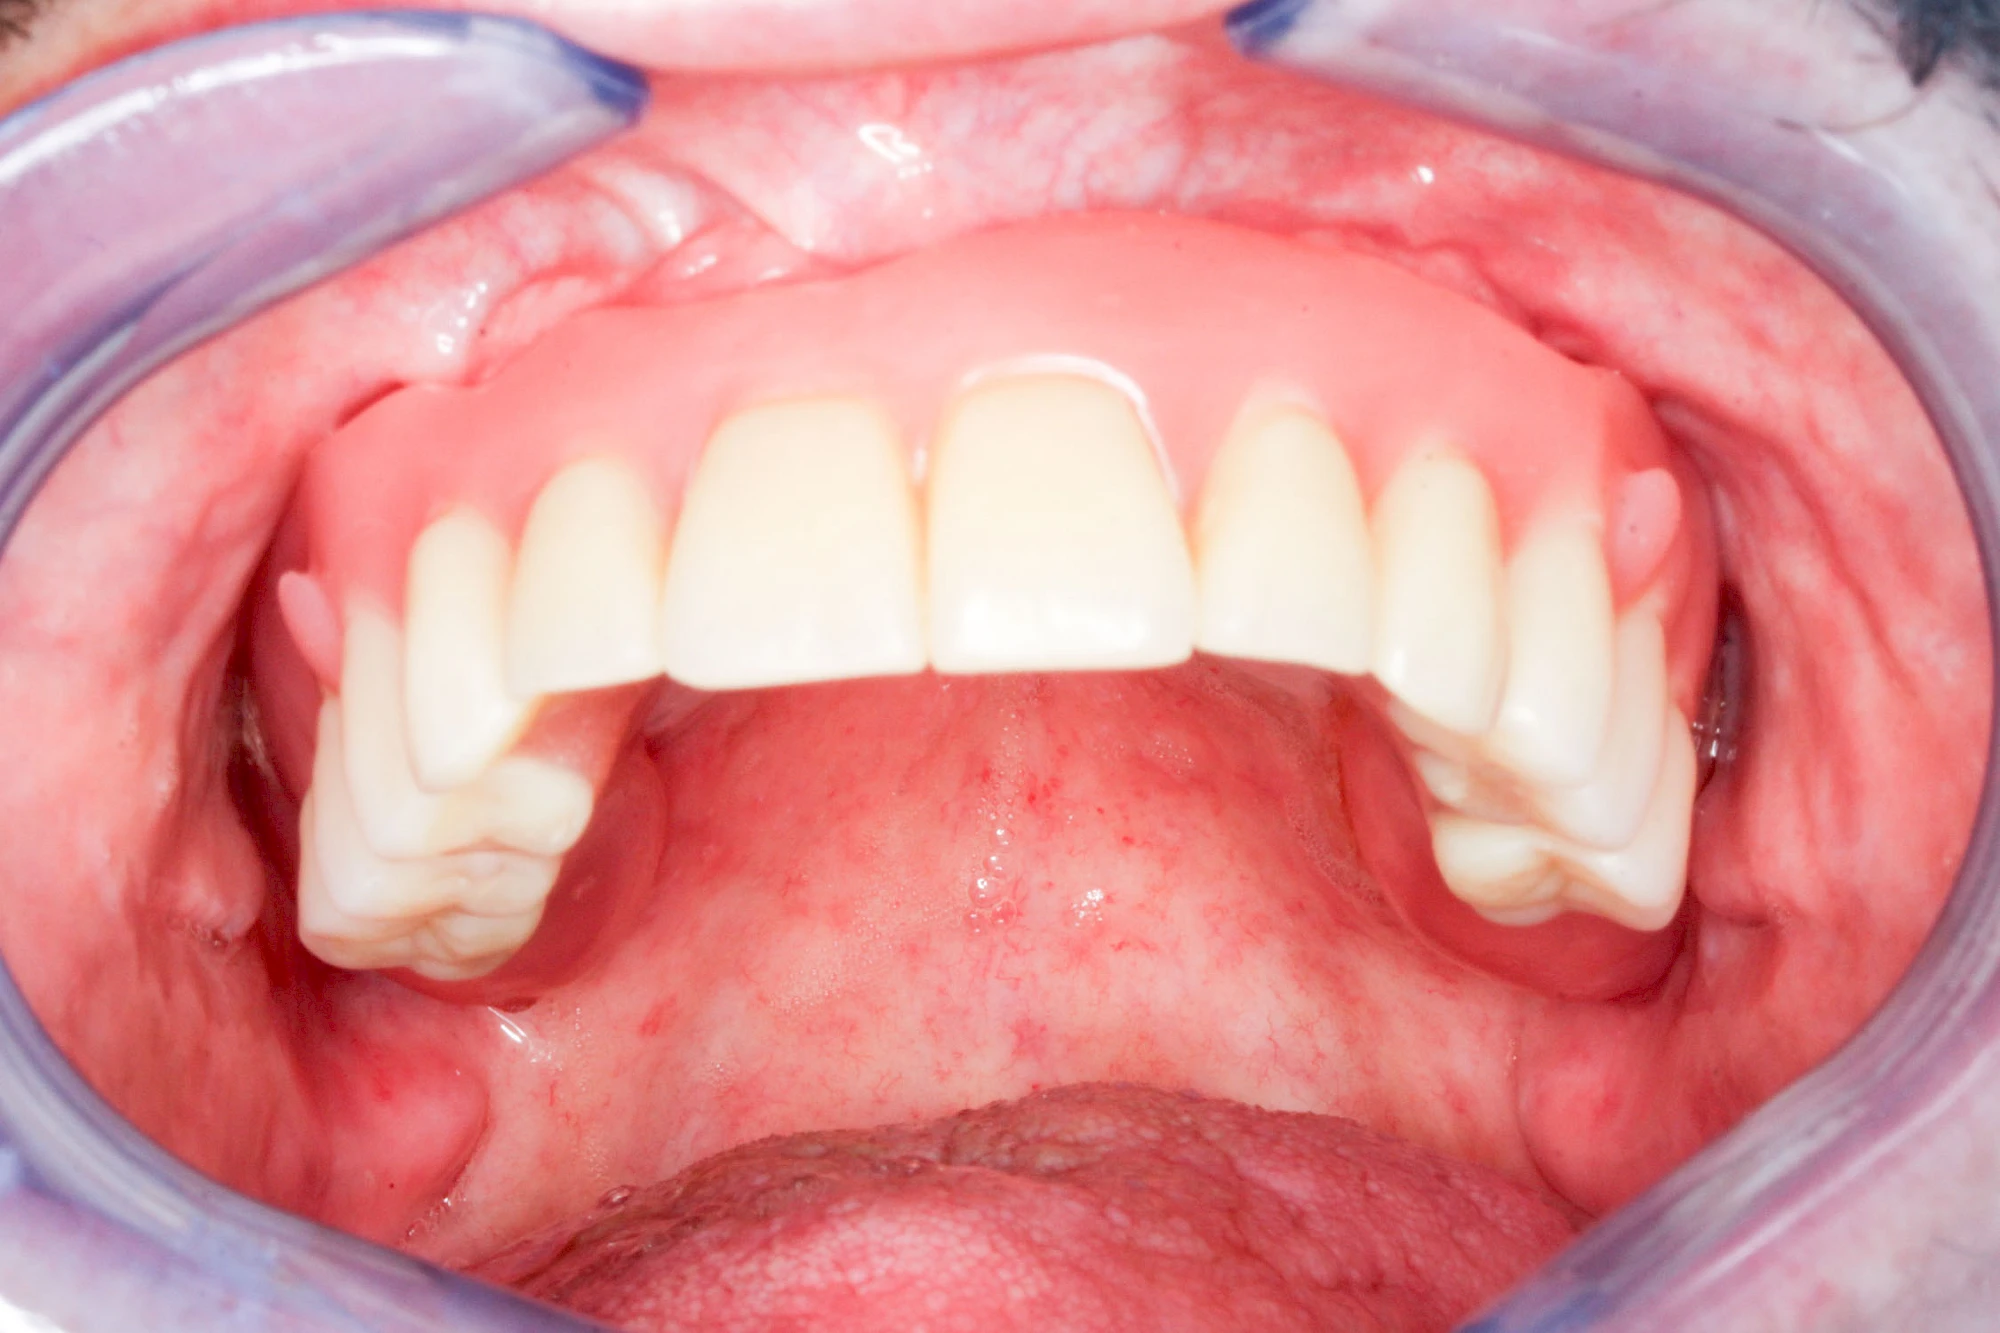

Implantate: Kronen & Brücken

Fehlen einzelne Zähne und die Nachbarzähne sind unbeschadet oder gut zahnärztlich versorgt, werden immer häufiger Implantate gewählt, um die Lücken zu schließen. Auch bei größeren oder verteilten Lücken, wenn keine herausnehmbare Prothese gewünscht ist, werden Implantate für Kronen- bzw. Brückenversorgungen gesetzt. In Einzelfällen entscheiden sich sogar zahnlose Patienten für eine festsitzende Versorgung auf Implantaten.

Varianten zur Verankerung von festsitzendem Zahnersatz auf Implantaten